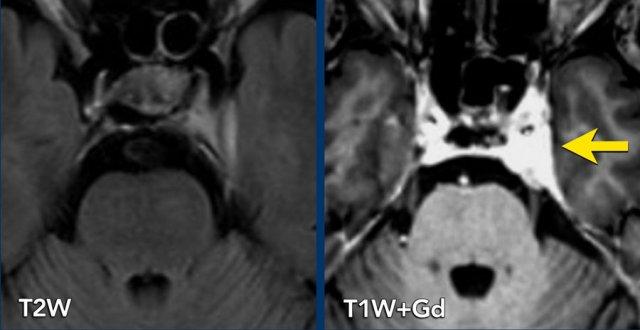

Bệnh nhân nữ 67 tuổi có tiền sử ung thư vú với di căn xương và gan. Bệnh nhân nhập viện với triệu chứng tê bì nửa mặt trái.

Hình ảnh FLAIR 2D axial cho thấy xoang hang không đối xứng, với dày màng cứng bên trái.

Hình ảnh sau tiêm thuốc tương phản từ cho thấy tăng ngấm thuốc ở xoang hang bên trái, lan rộng vào hang Meckel.

Hình ảnh nghi ngờ di căn của ung thư biểu mô tuyến vú.